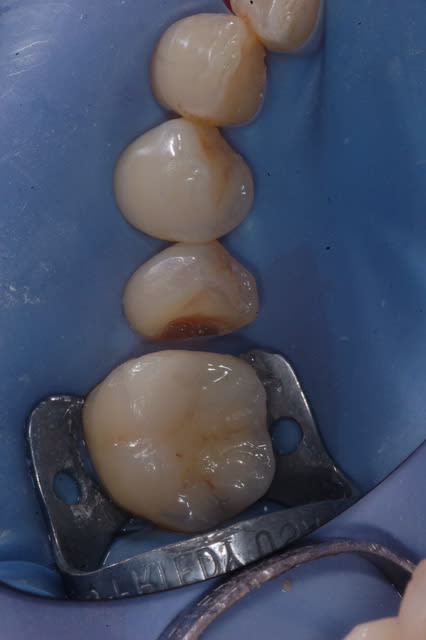

Un petit cas avec remontée de marche,collé au secure!

Voila pour ma contribution aux inlays.

Ma petite contribution.